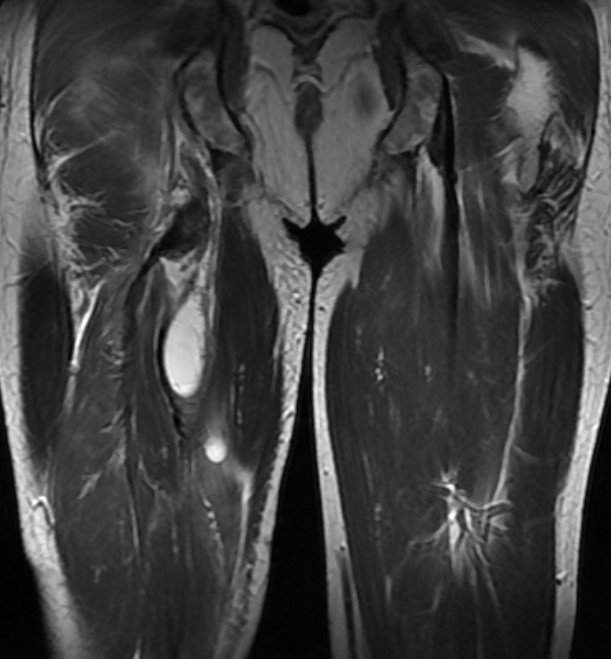

Bild: Universitätsklinik Balgrist

Hamstringverletzungen werden anhand einer klinischen Untersuchung und einer Magnetresonanztomographie (MRT bzw. engl. MRI für magnetic resonance imaging) diagnostiziert. In der klinischen Untersuchung fallen oft ein Bluterguss und Schmerzen am dorsalen Oberschenkel auf. Bei ausgeprägten Rupturen kann eine Delle im Verlauf der Hamstrings ertastet werden. Die Kraft bei Hüftstreckung oder Kniebeugung kann reduziert sein. Ein Röntgenbild ist typischerweise unauffällig, darauf könnte aber ein knöcherner Ausriss auffallen. Eine MRI-Untersuchung ist deshalb bei der Diagnose entscheidend, um das Ausmass der Verletzung zu quantifizieren (Retraktion, Grösse der Ruptur). Die Retraktion gibt an, wie weit sich die Sehnen von ihrem Ansatz am Tuber ischiadicum (Knochenvorsprung am Sitzbein) abgelöst haben.

Die Gradeinteilung der Hamstringverletzungen basiert auf der Klinik (Symptome) und dem Ausmass der Verletzung auf dem MRI-Bild:

- Grad 1: milde Symptome, intakte Sehnen

- Grad 2: moderate Symptome, Teilruptur der Sehnen

- Grad 3: schwere Symptome, Komplettruptur der Sehnen (alle drei Sehnen)